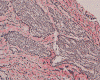

Pathology of the case:

The surgery removed several irregular fragments of tan, soft tissue for examination that were 2.5 x 1.2 x 1.0 cm in toto. Histologically, the lesion is a highly cellular neoplasm with tumor cells packed in solid sheets and without a specific architectural pattern (Panel D). Small, focal necrosis is also present (not shown). The tumor has rich vascularity and the endothelial cells seem to be active (Panel E). Almost all the tumor cells have only a thin rim of amphophilic cytoplasm, large nuclei with prominent nucleoli (Panel E and F). Clear cytoplasm is present in some tumor cells. In general, the cells do not look epithelioid or spindle. In some of the tissue fragment, the tumor shows invasion into the peripheral nerve root with dissection of the nerve fibers (Ú in Panel G and H). This phenomenon is well demonstrated by reticulin stain (Panel I) and immunohistochemistry for neurofilament proteins (Panel J). About half of the tumor cells are strongly positive for vimentin (Panel K). There is also scant positive tumor cells for S100 protein (Panel L) and cytokeratin AE1/3 (Panel M). The tumor cells are negative for neuorfilament proteins (Panel K) and smooth muscle protein (Panel N).